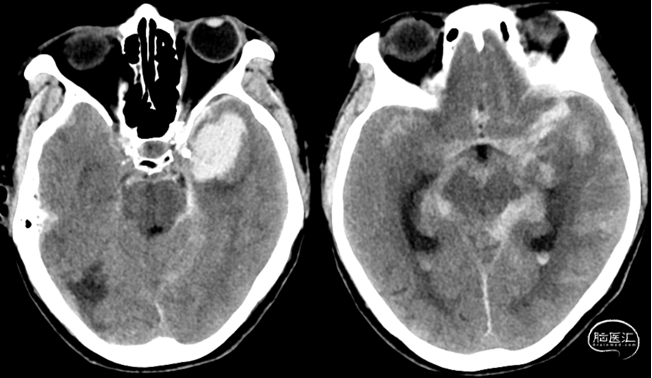

头颅CT

术前

术后第一天

术后第一天复查头颅CT

术后CT

术后CT